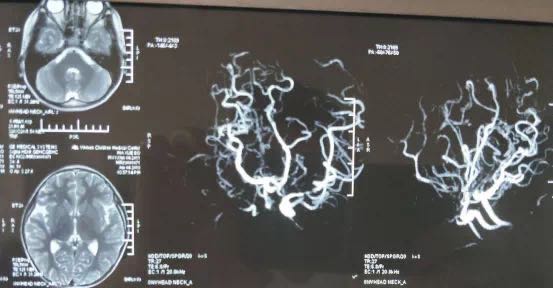

烟雾病的合并症有很多,那它到底会带来多大的危害呢?烟雾病分两类人群,一类是儿童,一类是成年人。儿童如果发现烟雾病不治疗的话,80%的儿童会有短暂性脑缺血的发作,胳膊、腿没有力量,说不出话,或者是发麻,头晕。还有一些儿童是癫痫发作,大概占10%,反复的抽搐,会对大脑造成一定的损伤。还有一小撮儿童是会发生脑出血,不过这类的孩子数量是比较少的。

大部分的儿童患有烟雾病,常见的症状就是一过性的肢体不好使,可能过几秒钟,几分钟就缓解了,很多家长难以发现,这个阶段如果不治疗或者是没检查出来,这个孩子可能近期就会导致脑梗塞。还有慢性缺血,虽然还没有导致脑梗,但是孩子长期大脑处于缺血状态,会导致智力低下、记忆力下降、学习能力下降,会有点像痴呆。在我们临床上见过很多儿童患者,五六岁的时候简单的做个手术治疗,七八岁再来的时候,孩子就“傻”了,问他什么问题都不懂,吃饭淌哈喇子,智力下降非常厉害。所以建议家长有发现孩子异常情况还是要去医院检查一下,如果发现烟雾病一定要尽早治疗,这不单是对孩子的未来考虑,也是为一个家庭的未来考虑。

至于成年人的话,不治疗的话,一般是会出现脑梗塞,可能导致一侧的胳膊、腿无力量,无法说话、昏迷、意识障碍等等,影响工作生活等,降低人们的生活治疗。还有更严重的就是脑出血了,严重到可能致死。所以不管是背负家庭重担的成年人,还是懵懂无知,未看清世界的儿童,发现烟雾病症状,尽早检查治疗,不要幻想着吃吃药就能康复。